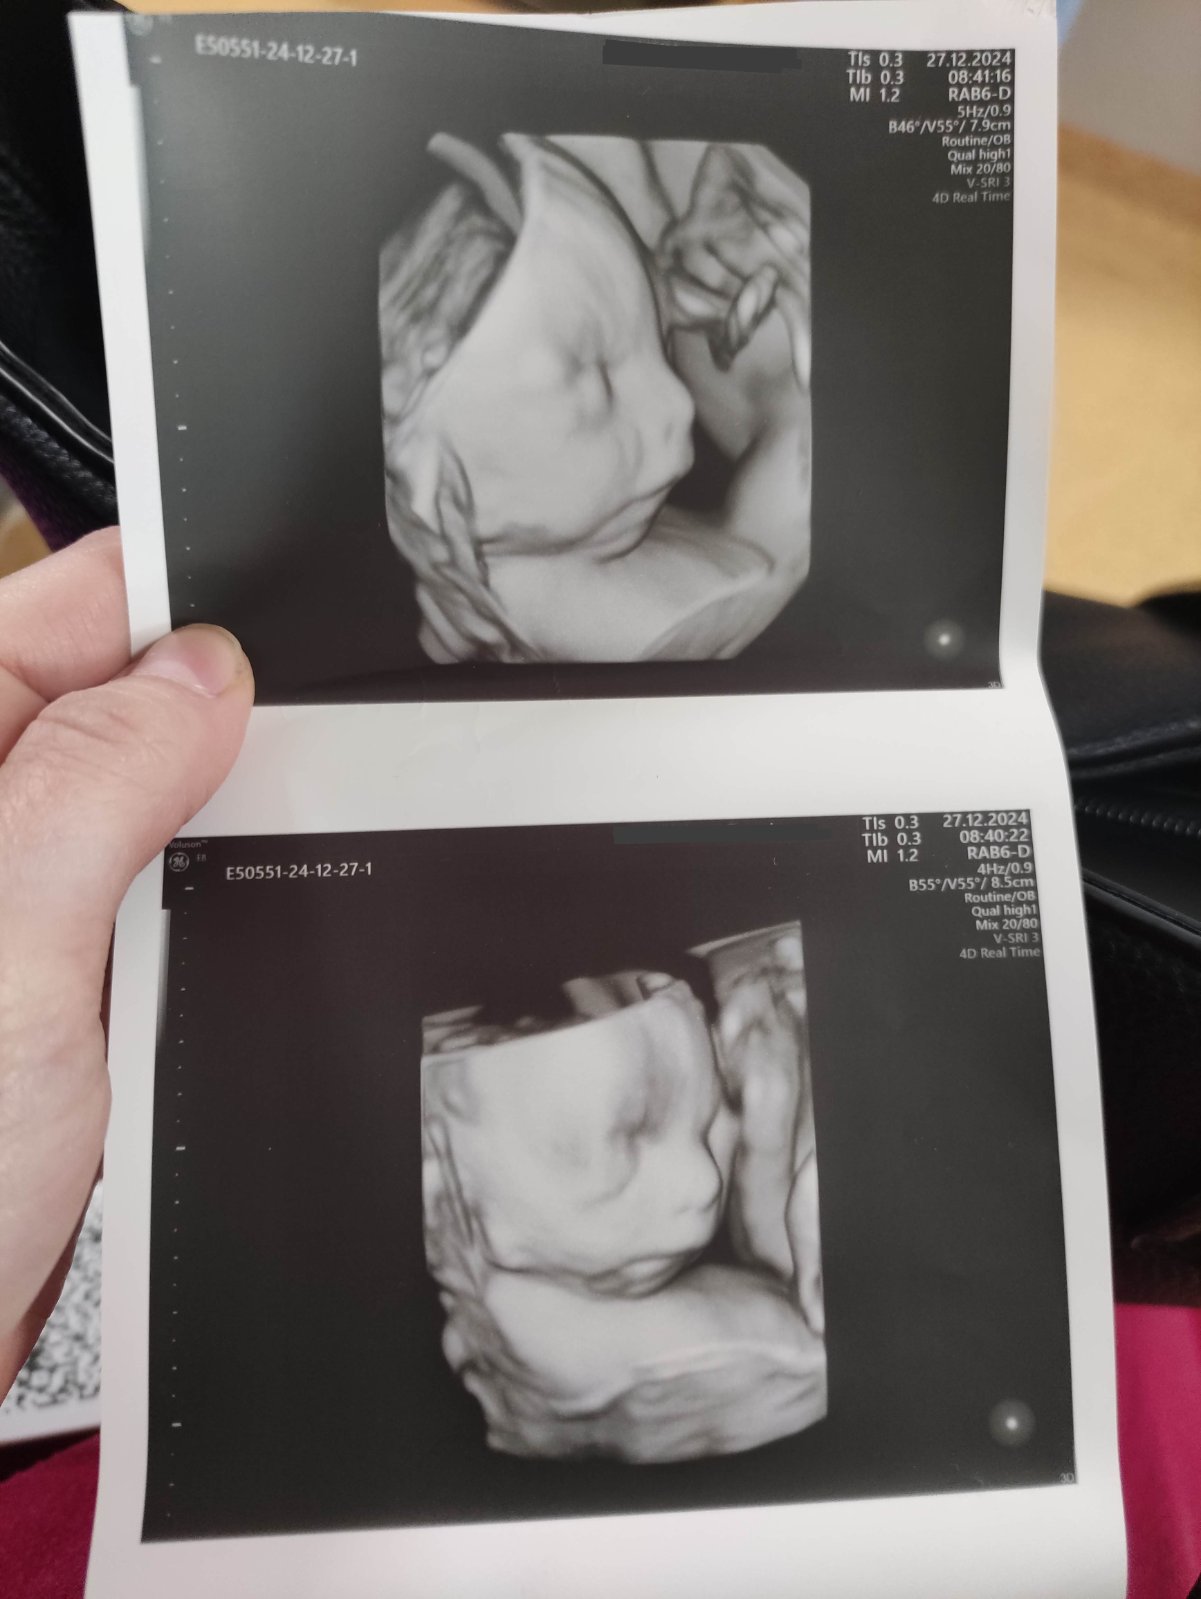

Doktor spravil v 24 tt. 4D sono bábätka. Zdá sa nám, že sánka nie je dostatočne vyvinutá oproti zvyšku tváričky. Lekár tvrdi, že podľa neho to je v poriadku. Myslíte, že sánka ešte dorastie, resp. máte prosím niektorá skúsenost, že bábätko malo menšiu sánku/bradu a potom postupne dorastla aj tá? 🙂 ďakujem ;)

@dasa1996 Este aj novorodenec ma vacsinou tu sanku taku vpadnutu a az po par mesiacoch su tam take lepsie neznaky buducej tvare.

Mňa toto s bradou kedysi vydesilo tiež a to som videla len 2D. Narodil sa uplne nádherný s rozkošnou malou bradou. Tvár sa mu mení stále a to má už 6 rokov.

Anooo aj nas maly to mal a este viditelnejsie, ako by nemal spodnu sanku na tychto foto. A je z neho kraaasny chlapec. Vsetko je ok neboj 😉

Dieťatko je v tekutine. Mimochodom, vyzerá úplne v poriadku. Nehľadajte problém tam, kde nie je.